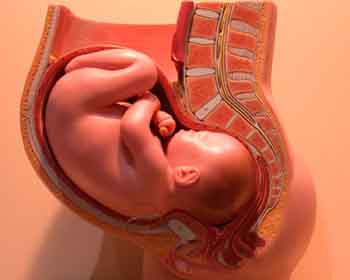

Embryo at 4 weeks after fertilization[1]

Fetus at 8 weeks after fertilization[2]

Fetus at 18 weeks after fertilization[3]

Fetus at 38 weeks after fertilization[4]

- ^ 3D Pregnancy (Image from gestational age of 6 weeks). Retrieved 2007-08-28. A rotatable 3D version of this photo is available here, and a sketch is available here.

- ^ 3D Pregnancy (Image from gestational age of 10 weeks). Retrieved 2007-08-28. A rotatable 3D version of this photo is available here, and a sketch is available here.

- ^ 3D Pregnancy (Image from gestational age of 20 weeks). Retrieved 2007-08-28. A rotatable 3D version of this photo is available here, and a sketch is available here.

- ^ 3D Pregnancy (Image from gestational age of 40 weeks). Retrieved 2007-08-28. A rotatable 3D version of this photo is available here, and a sketch is available here.